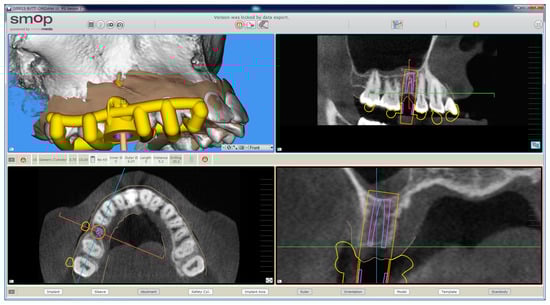

The planning of the case involved the use of two different sets of software: A prosthetic CAD (computer-assisted-design) (EXOCAD®, Darmstad, Germany) for the virtual wax-up and a surgical CAD (SMOP®, Swissmeda, Baar, Switzerland) for 3D planning of implant placement and the design of the surgical template (Figure 3).

Figure 3.

The implant is planned with the aid of a guided surgery software (SMOP®, Swissmeda, Baar, Switzerland). A 3.75 mm × 10 mm implant (BT Safe Bone Level®, BTK, Dueville, Italy) is therefore planned.

In the order, the .STL files deriving from the intraoral scan were imported into the prosthetic CAD, where the virtual waxing of the restoration (single crown or partial fixed prosthesis) was carried out, taking into account the volumes, shapes, and interproximal contacts of the adjacent and occlusal teeth with the antagonist arch. The file of the waxing was thus saved in a special folder, always as .STL, in order to be opened in the surgical CAD before planning the implant placement. At this point, the operator opened the surgical CAD software by importing the DICOM files derived from the patient’s CBCT. The software presented the different reconstruction planes (axial, coronal, and sagittal) and allowed the importation of the intraoral scan file (.STL) that was superimposed on the reconstruction of bone from CBCT. The superimposition was performed with care, first for points and then for surfaces, and controlled in each section. This phase was the most delicate of all, since a possible overlap error can undermine the planning and therefore the positioning of the fixture in the exact desired position. Once the quality of the overlap between intraoral scan and bone reconstruction by CBCT was carefully checked and verified, the operator identified the anatomical structures of risk (alveolar inferior nerve, maxillary sinus) and the design of the panoramic curve, in order to obtain the desired cross sections. The operator imported the .STL file of the diagnostic wax-up and proceeded to plan an implant of a length and a diameter appropriate to the recipient site, taking into accounts the residual bone anatomy and the important information derived from the wax-up. The implant was therefore planned in the best possible position, and prosthetically guided in relation to the residual bone anatomy. Particular attention was paid to the position and inclination of the fixture and its compatibility with the prosthetic emergence. In the case of patients requiring treatment with more than one implant, the same operations were repeated for each of the selected fixtures. At this point, parametric instruments allowed the clinician to establish the distance between the sleeve and the implant shoulder, depending on the height of the available gingiva: In accordance, from the length of the selected implant, and from the height of the sleeve (5 mm in the present study) derived the data related to the drilling depth, a key element in the surgical phase. Furthermore, the parametric tools of the software made it possible to adjust the width of the outside diameter of the hole in the template, for the insertion and fixation of the sleeve.

Since, in this study, the sleeves used were characteristic of an outer diameter of 6 mm, a certain degree of tolerance was established (0.07 mm) so that the diameter of this hole was fixed at 6.07 mm. After setting these key elements, the position of the implants was blocked and the operator switched to the surgical template design. A few simple CAD operators allowed the surgeon to draw an open selective tooth-supported surgical guide. The support was based on buccal and palatal (lingual) clamps and selective occlusal supports. The surgeon was free at this stage to regulate the degree of undercut of the clamps, and their size, as well as the dimensions and features of the occlusal and mucosal supports. This design phase was carried out in a simple but parametric way, allowing the surgeon to have total dimensional control of the components and shapes drawn. The peculiarity of these surgical templates was demonstrated by the fact that they were open, with selective supports on the dental surfaces, controllable in section, for a perfect verification of the adaptation on 3D-printed models and constant intraoral control during surgery. At the end of this process, the software calculated a surgical guide that was easily exported as an .STL file, upon payment of an export fee (with a variable price, in relation to the number of planned cases and exports requested).